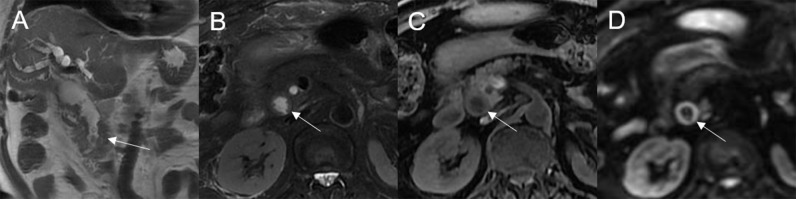

Mean lesion size in the whole sample was 30.83 ± 20.93 mm. All patients presented with an intraluminal ductal mass. While 14/32 (43.75%) lesions presented morphologically as focal eccentric-type masses (f3), 9/32 (28.13%) presented as plaque-like masses, 4/32 (12.50%) as bile duct casting masses, and 5/32 (15.62%) as infiltrative masses. In addition, 8/32 (21.88%) lesions showed a frond-like superficial appearance accompanied by other morphologically categorized appearances other than plaque-like superficial (f4, f5; T2).

On DWI (b = 800 s·mm-2), 5/32 (15.63%) adenomas showed isointensity (f2) and 27/32 (84.37%) showed hyperintensity. In 2/32 (6.25%) cases, the bile duct wall around the lesion showed hyperintensity on DWI (f8). The mean ADC value of the lesions was 1.65 ± 0.38 × 10-3 mm2·s-1 (T2).